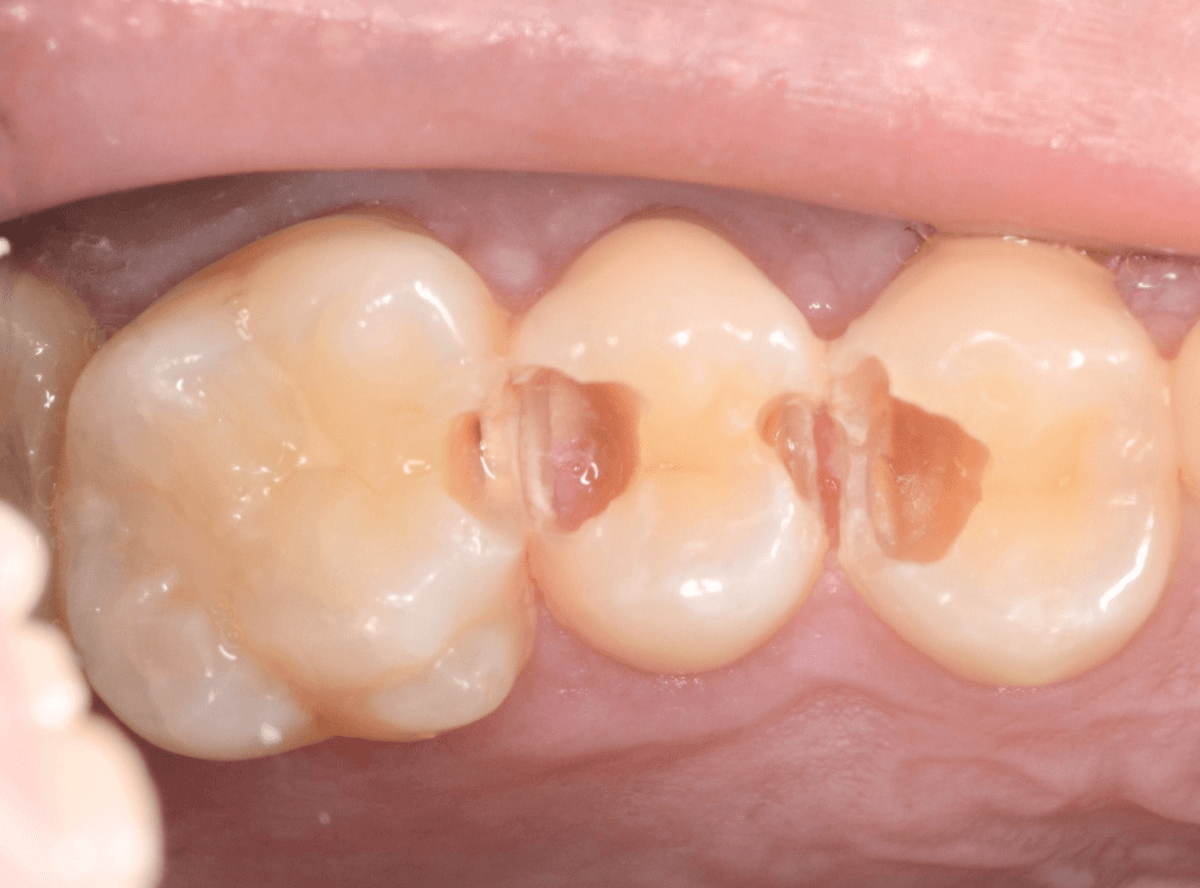

Case.22 痛みはないけど、歯のすきまから大きな虫歯

上の小臼歯の間が虫歯になっていた患者さんです。

症状はありませんし、見た目からも虫歯があるかはわかりませんでした。

全ての虫歯を除去しました。

レントゲン写真からある程度確認出来ましたが、歯の神経スレスレまで虫歯が進行していました。

ここまで虫歯が進行していても、全く症状を感じない事も多いです。

そして、ある時急に痛みを感じるのです。

虫歯は急に進行しません。

治療後の定期検診で確実に食い止めましょう。